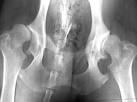

Cadera: La toma de las caderas por la enfermedad degenerativa articular adopta dos variedades:

- Coxoartrosis

primaria: En esta modalidad no se encuentra afectación previa de la cadera ni ningún otro hecho que predisponga a la aparición de cambios degenerativos en la articulación coxofemoral. Suele presentarse después de la cuarta década de la vida.

- Coxoartrosis secundaria:

Aparece en articulaciones predispuestas por algún padecimiento previo, como la displasia congénita, necrosis aséptica de la cabeza del fémur, artritis séptica de la cadera, etc. Todos estos cambios o alteraciones son los llamados cambios preartrósicos de Hockenbach. Se presenta en las primeras décadas de la vida y en ambos sexos, aunque parece estar favorecida por la menopausia.

Las manifestaciones clínicas suelen ser bilaterales, aunque generalmente los síntomas predominan en una articulación. Los pacientes refieren que comenzaron a sentir sensación de cansancio o dolor en la región inguinal afectada, el cual aparecía durante la marcha y aumentaba su intensidad con las sobre cargas, como subir escaleras, acompañado de sensación de rigidez en la articulación. Posteriormente el dolor de intensificó, sobre todo al reiniciar la marcha después de un reposo prolongado. Este dolor puede irradiarse a la cara anterolateral externa del muslo y con menor frecuencia a la cara interna de la pierna.

El examen físico demuestra limitación en los movimientos articulares y dolor que se irradia hacia la pantorrilla en su porción media cuando se levantan peso.

Con el decursar de la enfermedad el paciente adquiere una actitud en la cual mantiene la pierna en flexión, con rotación externa y abducción, así como el torso inclinado hacia delante y hacia el lado enfermo. La mayoría de los enfermos quedan seriamente incapacitados, debido al dolor y a la restricción de los movimientos articulares.

Radiología: Cualquiera que sea la articulación tomada por la enfermedad degenerativa articular, el hallazgo de osteofitos marginales es un hecho frecuente y característico. En los estadios iniciales de la enfermedad se suele encontrar destrucción del cartílago interarticular, que se traduce radiológicamente por el estrechamiento de la interlinea. En el hueso periarticular pueden verse quistes radiotransparentes de tamaño variable, desde unos milímetros hasta varios centímetros.

Cuando la enfermedad lleva tiempo de evolución, en la articulación dañada se puede encontrar una radiocondensación acentuada, a consecuencia de la calcificación del cartílago y de la presencia de hueso de neoformación, que en ocasiones obliga hacer el diagnóstico diferencial con las tumoraciones óseas, sobre todo metastásicas.